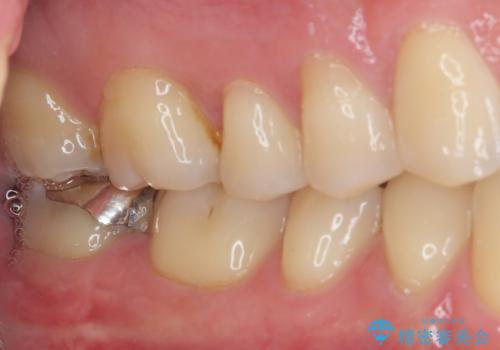

最後の確認方法として、局所麻酔を行わずに最後臼歯の銀歯を外し、神経組織近くまで歯質を切削したところ痛みなどを全く感じず、その後無菌的環境下にて切削を進めたところ、神経組織の一部が壊死していることが確認されました。

その後は速やかに根管治療を行い、初回の処置以降は痛みや違和感が一気に引いたため、根管治療後にオールセラミッククラウンにて補綴治療を行うこととしました。